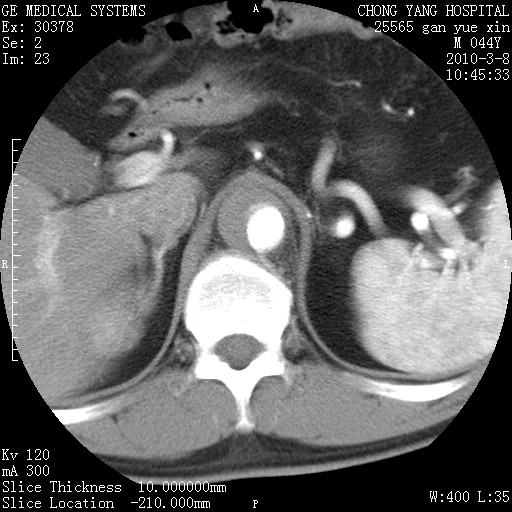

标题: CT24940:主动脉增强,典型病例。 [打印本页]

标题: CT24940:主动脉增强,典型病例。

夹层动脉瘤。

动脉夹层

夹层动脉瘤,典型

主动脉夹层。

动脉夹层的分型:

⒈debakey分型:根据主动脉夹层累及部位,分为三型:ⅰ型:原发破口位于升主动脉或主动脉弓部,夹层累及升主动脉、主动脉弓部、胸主动脉、腹主动脉大部或全部,少数可累及髂动脉。ⅱ型:原发破口位于升主动脉,夹层累及升主动脉,少数可累及部分主动脉弓。ⅲ型:原发破口位于左锁骨下动脉开口远端,根据夹层累及范围又分为ⅲa,ⅲb。ⅲa型:夹层累及胸主动脉。ⅲb型:夹层累及升主动脉、腹主动脉大部或全部。少数可累及髂动脉。

⒉stanford分型:a型:夹层累及升主动脉,无论远端范围如何。b型:夹层累及左锁骨下动脉开口以远的降主动脉。

夹层动脉瘤,少量胸水

夹层动脉瘤;左侧少量胸腔积液。

典型主动脉夹层。